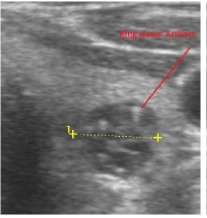

In our study many patients were found to have nodules look very much like PT adenoma, Figure 7 below. At least, 4 patients were subsequently confirmed to have parathyroid adenomas, Figure 8 and 2 patients underwent surgery

Despite the fact that nodular pathology was found to be very prevalent among our study population, it has been found difficult to differentiate between thyroid and parathyroid pathology using ultrasound alone. However, some characteristics of the parathyroid glands might suggest parathyroid pathology in the context of the clinical picture of secondary or tertiary hyperparathyroidism which is very prevalent in ESKD patients’ populations.

Figure 7.Thyroid nodule suspicious for Parathyroid adenoma due to its location